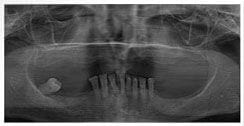

X 光片

術前X光片

術後X光片